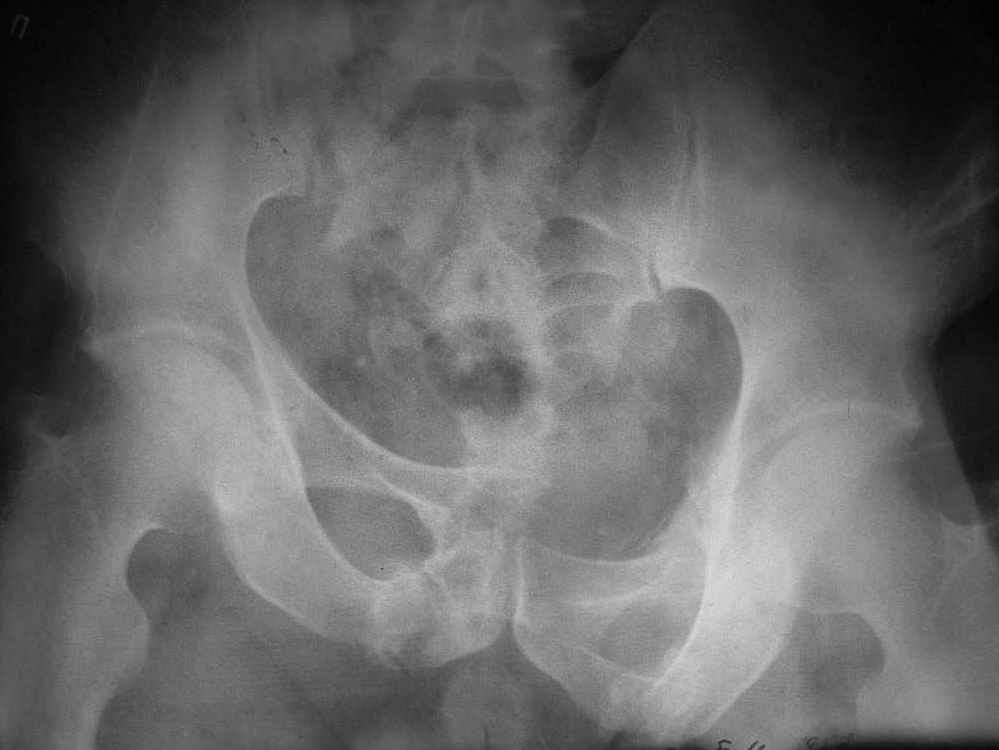

Пример лечения стабильной деформации с вертикальным смещением половины таза.

отеотомия передних и задних отделов, дистракция аппаратом